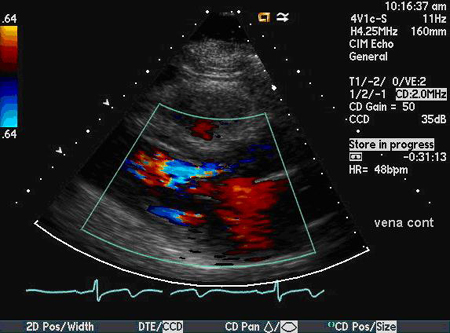

Dopplerfluxometria colorida

Uma das técnicas mais específicas e sensíveis usadas para julgar a gravidade do fluxo regurgitante, que usa a relação entre a largura do jato proximal e a via de saída do ventrículo esquerdo e a relação entre a área transversal do jato e a via de saída do ventrículo esquerdo. A vena contracta, que é a região mais estreita do jato regurgitante logo abaixo da valva aórtica, também pode ser usada.[24][Figure caption and citation for the preceding image starts]: Incidência do eixo paraesternal longitudinal demonstrando largura e altura de jato de regurgitação aórticaDos acervos Dr. Sanjeev Wasson e Dr. Nishant Kalra; usado com permissão [Citation ends].

[Figure caption and citation for the preceding image starts]: Incidência do eixo paraesternal longitudinal mostrando vena contracta do jato de regurgitação aórticaDos acervos Dr. Sanjeev Wasson e Dr. Nishant Kalra; usado com permissão [Citation ends].

Incidências paraesternais têm preferência sobre a incidência apical devido à melhor resolução axial.